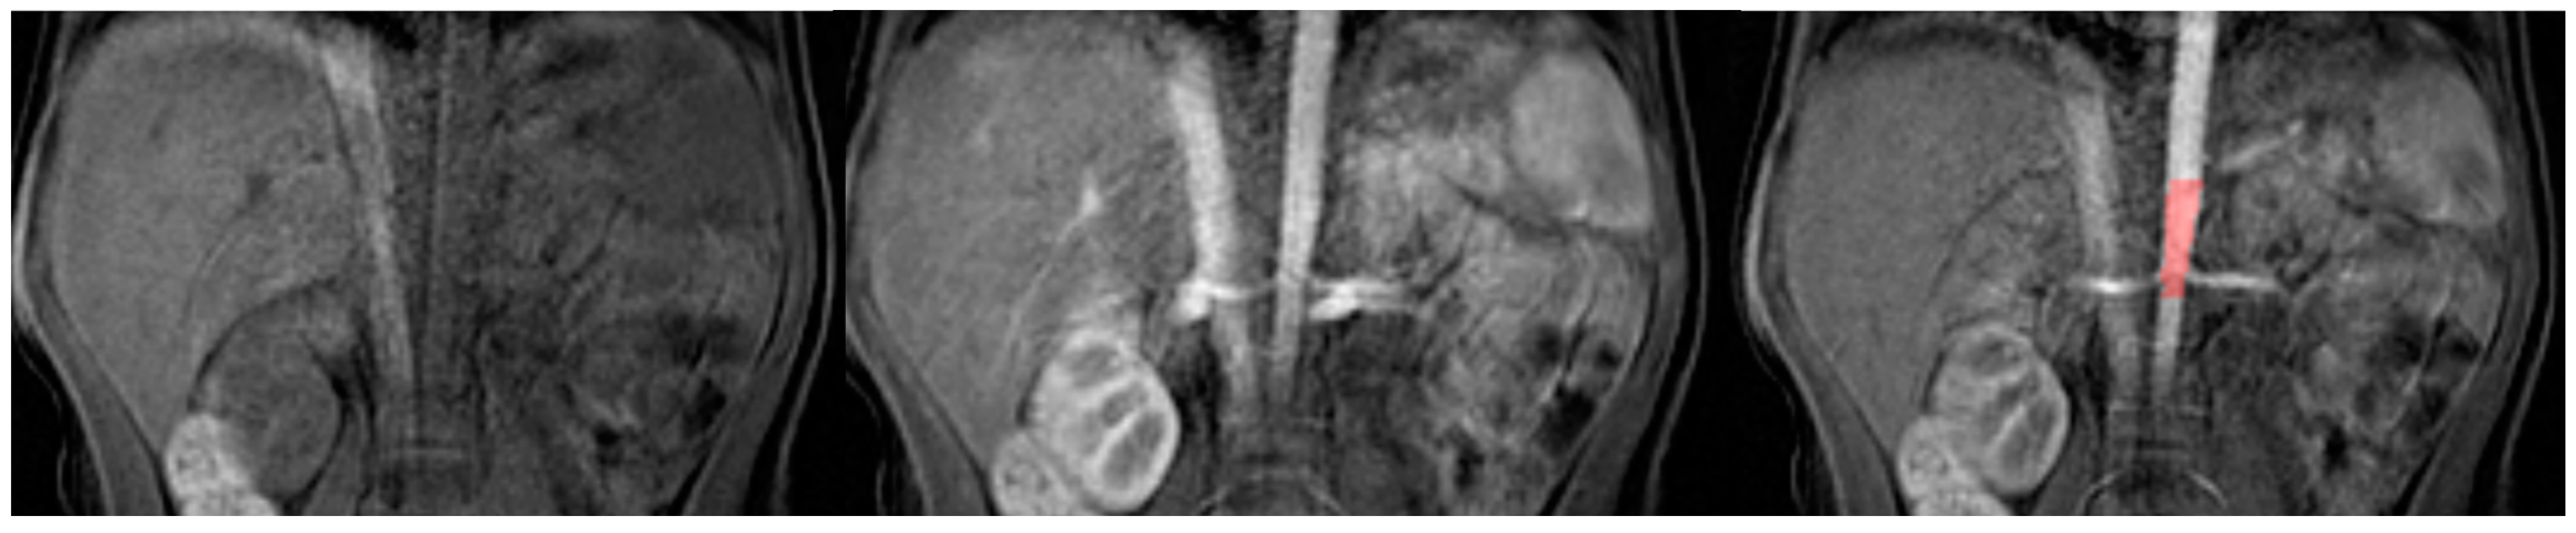

- Separation of the aorta (Figure 3)—the number of time points was found so that the aorta was marked significantly against the background of the organs (the moment of the highest signal intensity in the vessel),